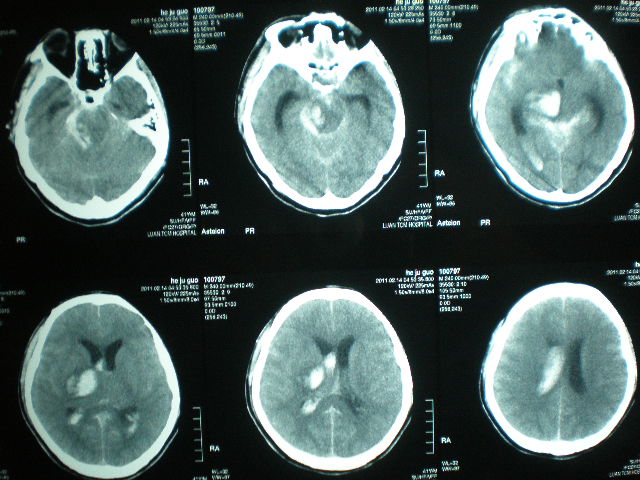

病例一

患者徐某某 、女、55歲、家住濰坊市經(jīng)濟開發(fā)區(qū)馬家埠村。2008年3月5日,患者被家屬發(fā)現(xiàn)突然意識不清,呼之不應(yīng),惡心、嘔吐,右側(cè)肢體癱瘓。由120車接到市立醫(yī)院。做顱腦CT后診斷“腦出血”。及時做腦出血微創(chuàng)手術(shù),病人轉(zhuǎn)危為安。12天后病人能自己吃飯、穿襪子、穿鞋,自己走出病房出院。病人及家屬送錦旗表示感謝。

病例二

患者玄某某、女、90歲,家住濰坊市經(jīng)濟開發(fā)區(qū)邢石村。2014年3月13日,患者突然感到眩暈,之后重重摔倒在地,出現(xiàn)昏迷,家屬發(fā)現(xiàn)后撥120,120急救車將患者接到市立醫(yī)院?;颊叱霈F(xiàn)呼吸不規(guī)整,有時呼吸暫停,瞳孔不等大,瀕臨死亡的邊緣。做顱腦CT后診斷“腦出血”。當即決定做腦出血微創(chuàng)手術(shù)。10天后患者意識清醒,出院。

? 1、病人頭部備皮,閱讀腦出血病人第一張顱腦CT片,以CT片OM線為基線,畫出腦出血最大出血層面在頭皮的位置線,在此線上測出前額至血腫中心的距離,初步確定穿刺到達血腫中心在顱腦頭皮位置點。并貼金屬片做標記。

? 2、手術(shù)前再做一次顱腦CT,以觀察血腫有無增大。觀察初步確定的穿刺點是否準確,再次做調(diào)整,確定頭皮穿刺點。